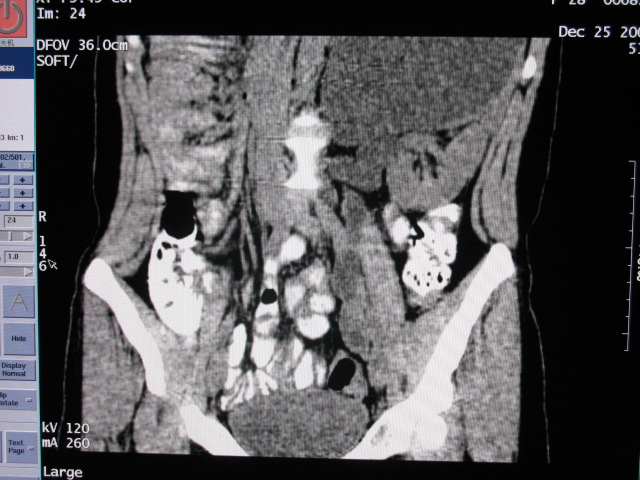

女,28岁,自觉腹部包块一年余

左侧为扩张的输尿管,一直延续到膀胱,那么它的上端应该是扩张的肾盂,但是在他的下方我们看到一个比较正常的肾,所以考虑左侧重复肾盂输尿管畸形。

考虑左侧双肾盂双输尿管畸形,其中一输尿管末端梗阻(不排除异位开口可能)并相应之肾盂及输尿管明显扩张积水。

左侧重复肾、双输尿管畸形。重复肾一般上位肾发育不良,易合并积水。

考虑左侧双肾盂双输尿管畸形,其中一输尿管末端梗阻(不排除异位开口可能,不知病人有无不自觉溢尿,有可能开口于阴道或宫颈,也可下端为盲端)并相应之肾盂及输尿管明显扩张积水。

术后证实是左侧双肾盂双输尿管畸形,巨输尿管巨肾盂症